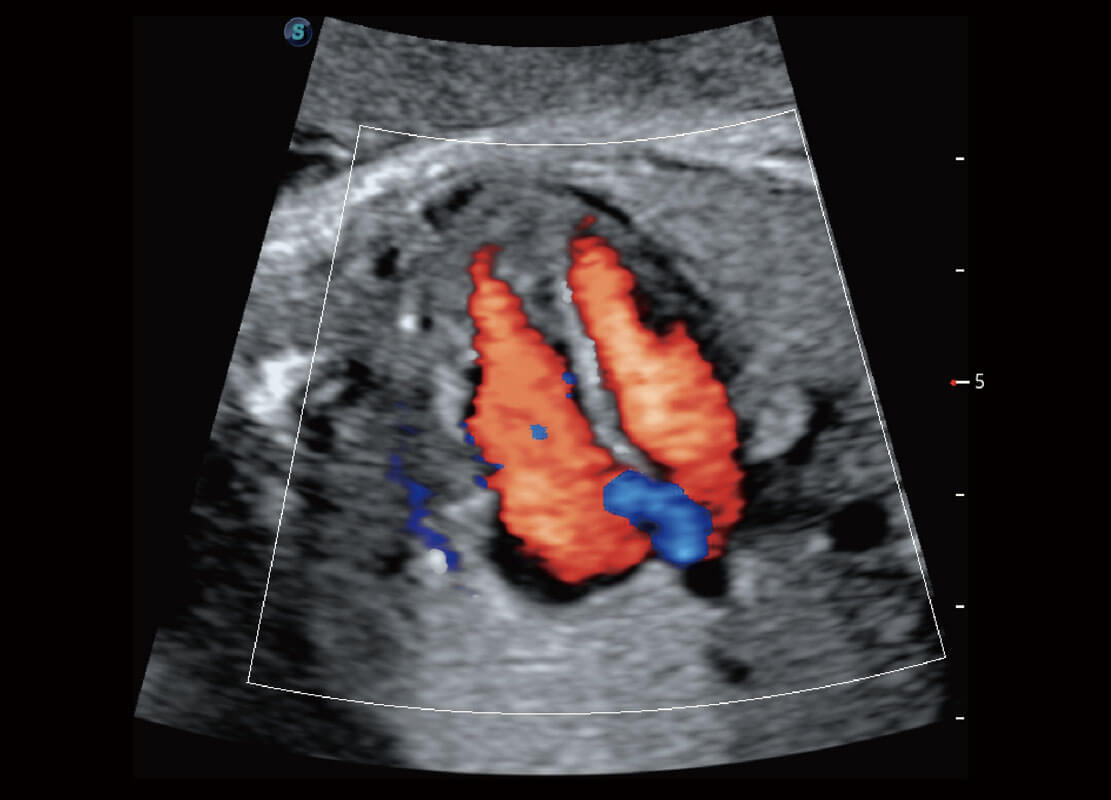

P60优异的图像质量搭载专科探头,在妇科基础疾病的诊断、卵泡生长的监测、输卵管通畅情况的判别等方面为您提供生殖应用方案。

腔内妇科-宫腔分离